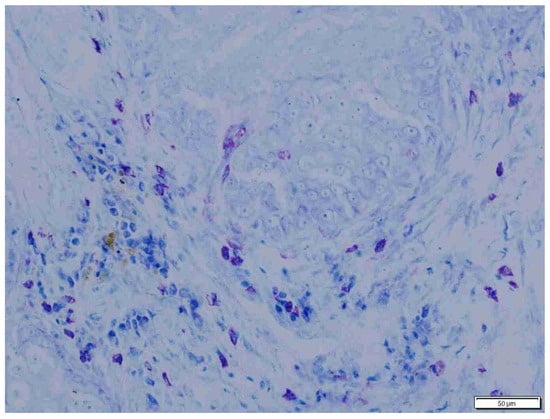

3. Results